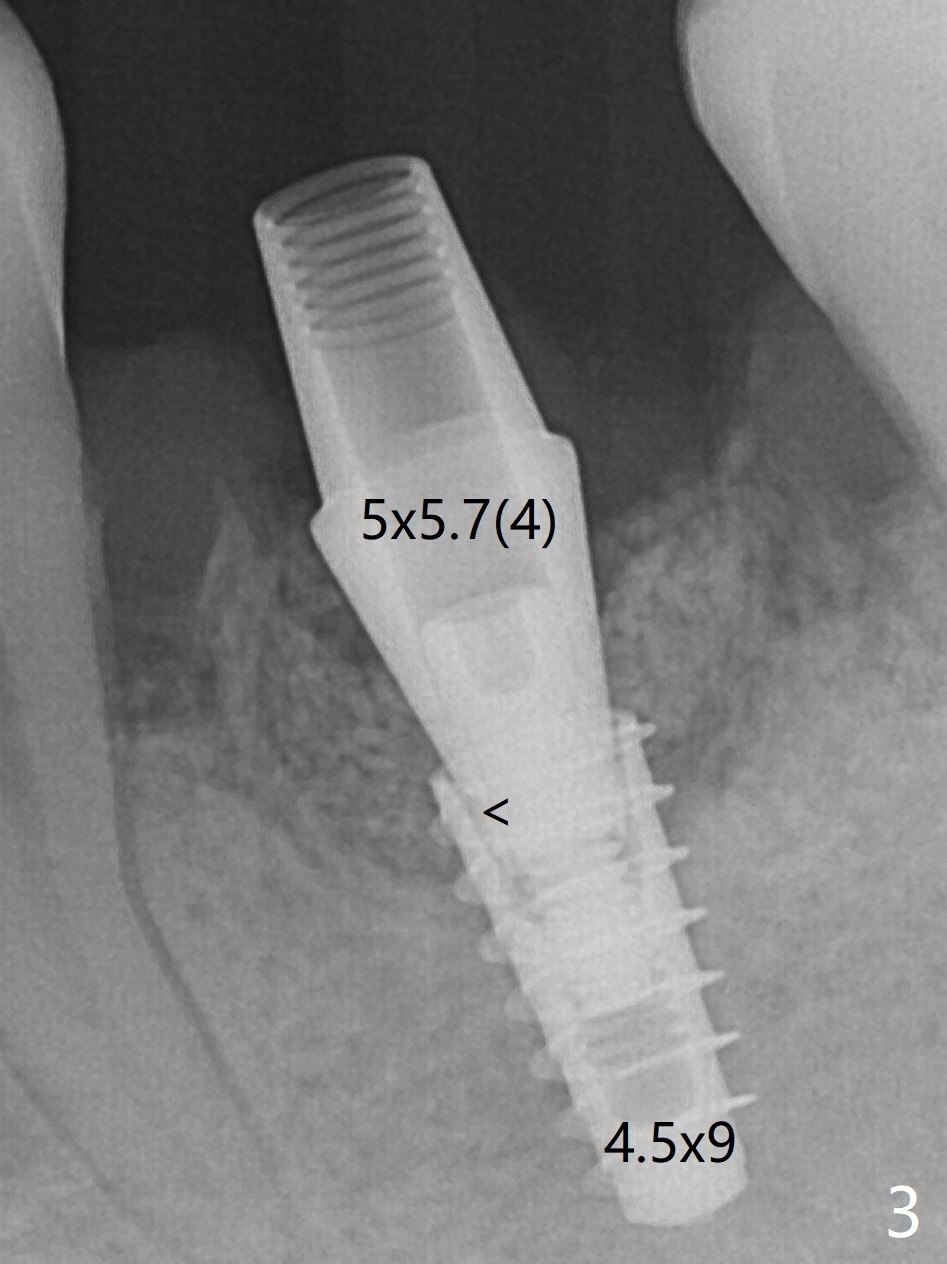

In spite of smoking reduction (1ppwk), the infection at #19, including buccal fistula (Fig.1 <) seems to be so severe that it affects pain threshold. Local anesthetics have to be added, including Bupivacaine IANB. When 4x10 mm drill is being applied, the patient feels pain. The plan is to use 4x11.5 mm drill as a final one. A 4x9 mm dummy implant is placed with 2.8 mm implant exposed (Fig.2 >), but it is subcrestal mesiodistally. Primary stability of a definitive 4.5x9 mm implant is satisfactory (Fig.3), but after initial bone graft, a 5x5.7(4) mm abutment is unable to be seated completely (<). Following 4.6 and 5.6 mm bone profile drills, the abutment remains incompletely seated (Fig.4). After fine turning, the abutment is fully seated; final round of bone graft (sticky bone) is placed mesiodistally (Fig.5 *) and buccolingually (Fig.6,7). It appears that there is tight fit between IBS implant and abutment. It is hoped that the excess bone graft with PRF is able to cover the coronal portion of the implant. If not, socket preservation should be done in this situation. In fact the implant is not placed lingual enough as compared to the design (Fig.6'). A 4.5 mm cortical drill should be used in a crown down fashion. In fact there is bone coverage coronally 5 months postop (Fig.8). Return to Prevent Molar Periimplantitis (Protocols, Table) No Deviation 12/14 Xin Wei, DDS, PhD, MS 1st edition 02/11/2020, last revision 06/30/2020